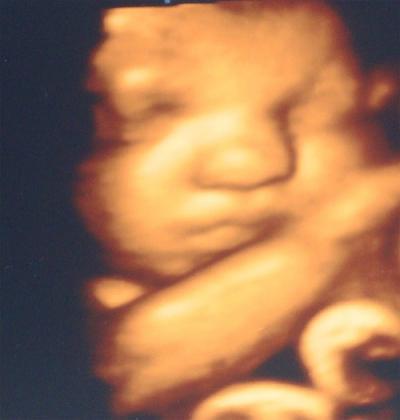

Heute war ich bei der VU, soweit alles gut...nur beim CTG ist der Herzschlag bei 120 gewesen, weniger darf es nicht werden. Der kl. Maus geht es gut, mache mir aber trotzdem Sorgen... VLG Anne Ach ja, auch Schwangere die Arbeitslos sind bekommen Geld von der Krankenkasse, so hoch wie das Arbeitslosengeld ist...zumindest bei der DAK...

Was ein süßes Foto :) Sie sieht richtig knuffig aus...

Süßes Foto und schön dass bei der VU alles ok war! War sie die ganze Zeit bei 120??? Drück die Daumen dass es beim nächsten Mal wieder besser ist - vllt. hat sie ja nur geschlafen??? GLG

Oh ne ganz süsse Maus hast du da und schön das bei der VU alles ok war das liest man doch gerne Glg Nadja mit Liam im Bauch der gerade wieder ne Turnstunde hat 33+1 SSW

hallo, die 3D-bilder finde ich echt faszenierend, sieht total süß aus.

Das ist es ja, die kleine Maus war wach und hat immer wieder nach den Kontaktknpöfen getreten. Sie war hellwach, selbst als ich mich auf die Seite gelegen habe blieb es bei 120 mit dem Herzschlag....Mal sehen was nächste Woche beim CTG raus kommt. Plazenta, Nabelschnur und Herz sind aber in Ordnung. Komisch, woran das wohl liegt? Ich habe keine Ahnung.